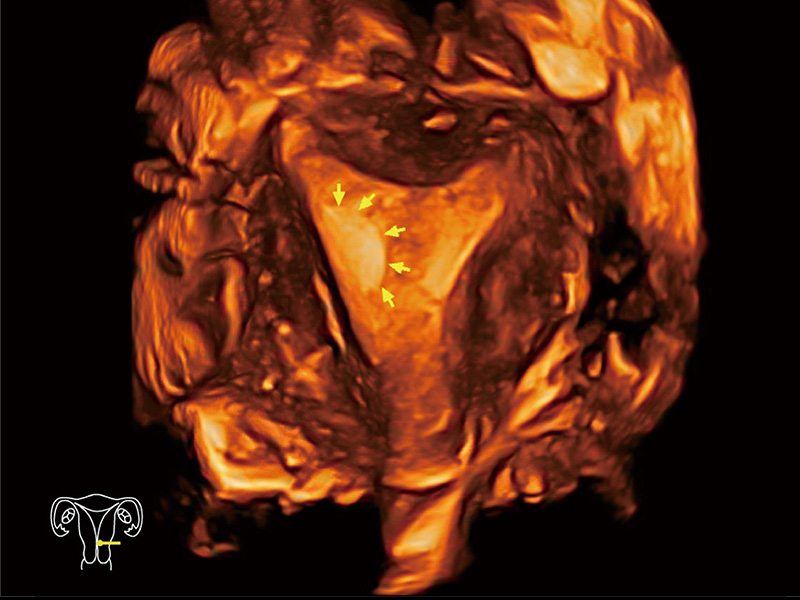

中央型宫腔粘连

单角子宫